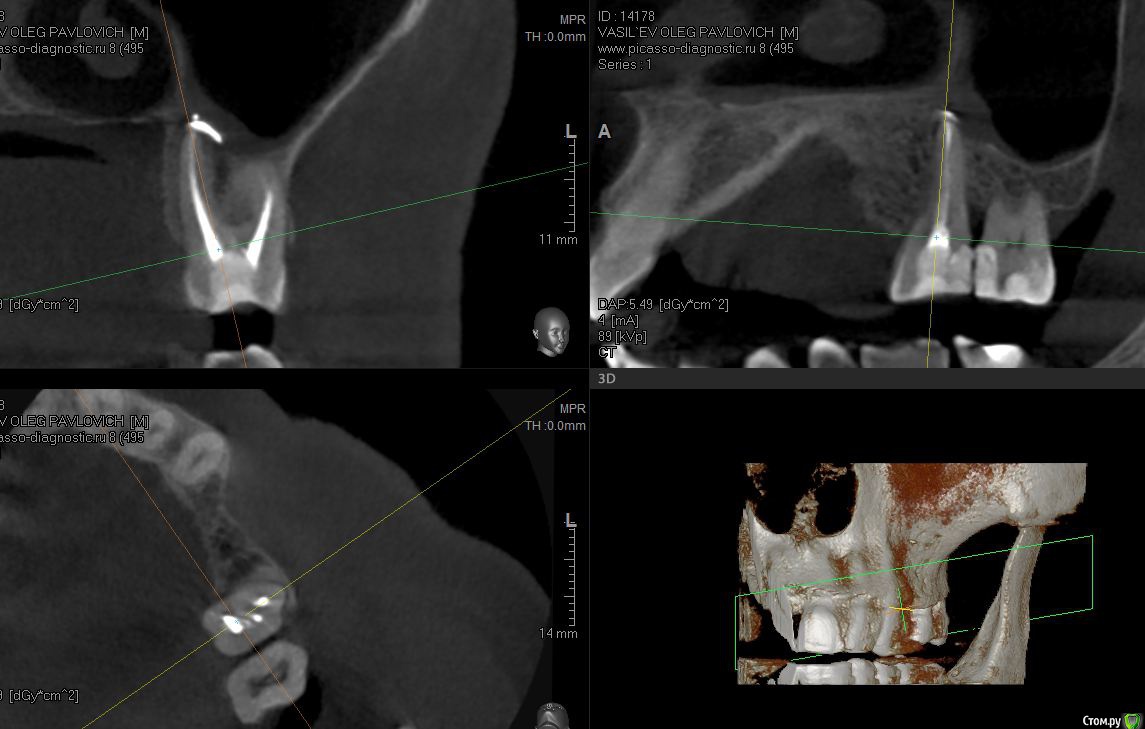

sugaka30 Опубликовано 7 января, 2017 Автор Поделиться Опубликовано 7 января, 2017 (изменено) Сделал Кт Может кто прокоментирует Не пора ли мне Пора? А то что то мне все плохеет https://yadi.sk/d/RXxAPdk237XVpi Заранее спасибо Изменено 7 января, 2017 пользователем sugaka30 Ссылка на комментарий

sugaka30 Опубликовано 7 января, 2017 Автор Поделиться Опубликовано 7 января, 2017 И скажите все таки есть перфо материала в гайморову или пронесло? Ссылка на комментарий

sugaka30 Опубликовано 22 января, 2017 Автор Поделиться Опубликовано 22 января, 2017 Проконсультируйте пожалуйста по этим срезам А то местный хирург не может понять что не так Ссылка на комментарий

St. Опубликовано 22 января, 2017 Поделиться Опубликовано 22 января, 2017 Скрины кт в обл леченного зуба Ссылка на комментарий